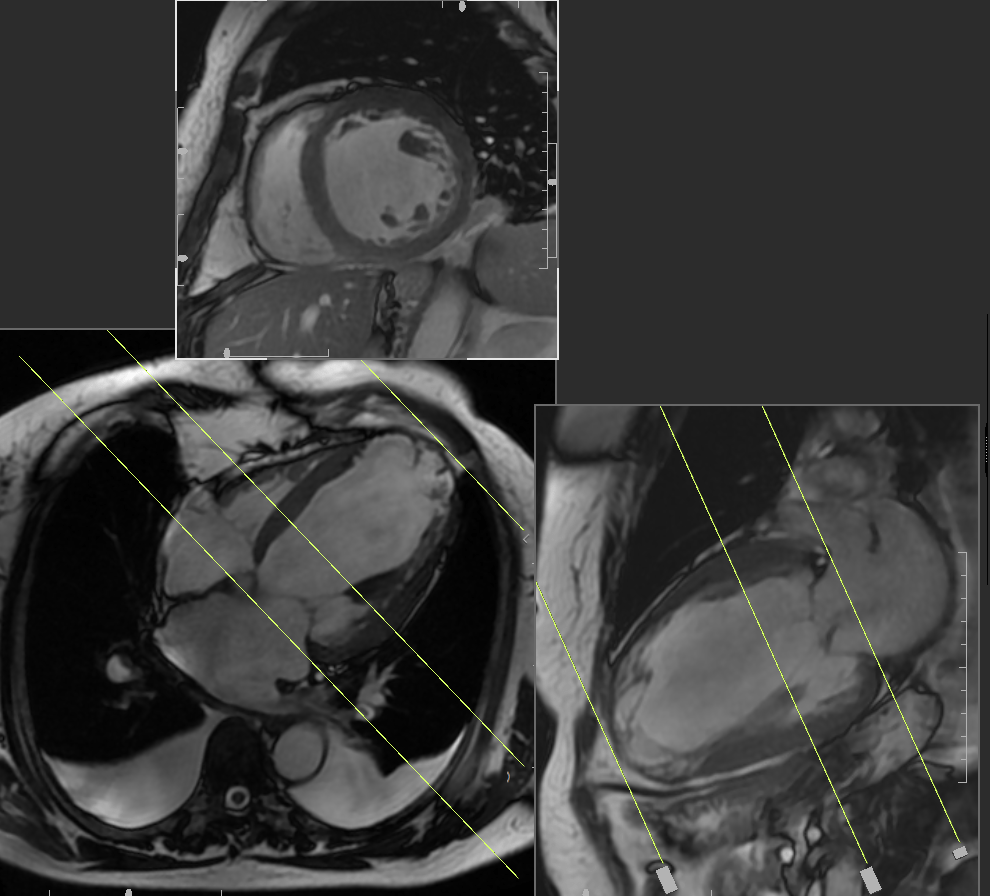

Cardiac Magnetic Resonance Imaging CMRI

The Cardiovascular Phenomics Core Laboratory experts provide comprehensive cardiac magnetic resonance imaging (CMRI) functional, perfusion and viability analyses that includes:

- Left ventricular (LV) and right ventricular (RV) function quantification

- Anatomy and tissue segmentation

- Signal intensity analysis for the myocardium and infarct sizing